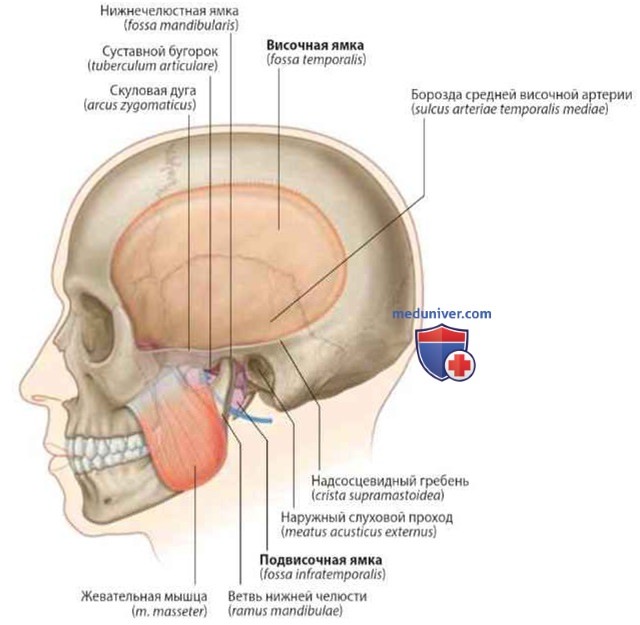

Анатомические особенности: фотографии ямок черепа, височной и подвисочной крылонебной